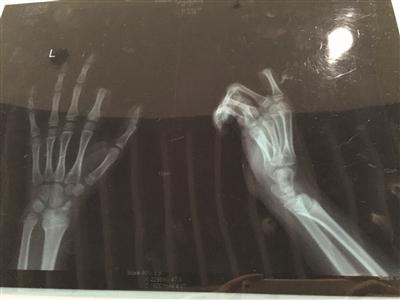

X光片显示孩子食指两个指节被切断

手术历经3个多小时。若能顺利度过一个星期的危险期,接上去的手指便能成活。苏州大学附属瑞华医院手外科主任周荣是小朋的主刀医生。下午1点不到,小朋便被推进手术室做准备,下午4点左右,小朋才被推出了手术室,转入病房。不幸中的万幸,经过三个多小时的手术,小朋的手指被暂时接上。小朋的父母都没想到孩子会做出如此举动,看到手指掉下来了,都愣住了。随后,二人又立刻反应过来,将断指用纸包好,放进口袋,带着小朋便赶到了医院。

周荣说:“孩子年纪太小,血管也非常细,所以手术难度比较大,现在,手指已经被接上了,接下来便看他的恢复情况了。”据周荣介绍,手术后,小朋的手一定不能乱动,否则很容易造成血管堵塞。如果小朋的配合程度高,顺利度过了一个星期的危险期,接上去的手指成活了,那么,这次事故对小朋今后生活的影响应该不大。